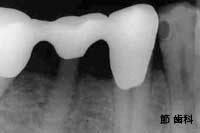

② これは右上の奥歯を2本連続して失った部位に対して、最後臼歯部分にT字型をした“人工サファイヤ”タイプのインプラントを施し、その手前の2本の歯とブリッジ状に連結する事で欠損補綴を行っています。やはり、上記と同時期のものです。